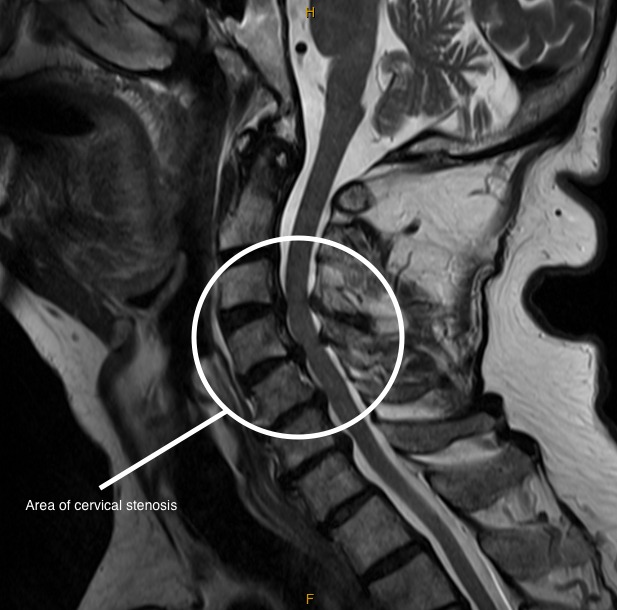

RMN / imagine stenoză de canal vertebral

Exemplu imagistic: stenoză de canal (cervicală).